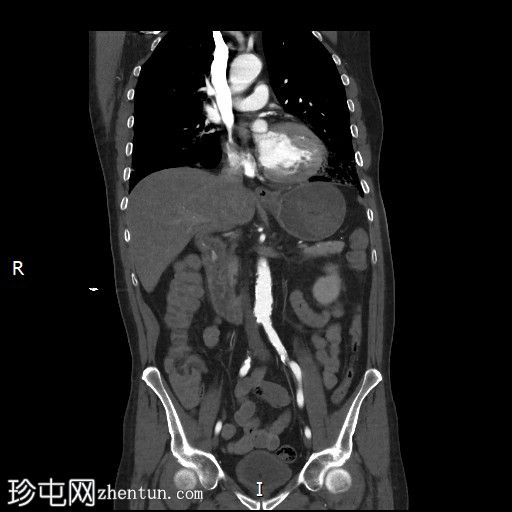

冠状位增强扫描

动脉期

门静脉期

十二指肠第三段造影剂积聚

活动性出血

CT血管造影对检测活动性消化道出血具有较高的敏感性。